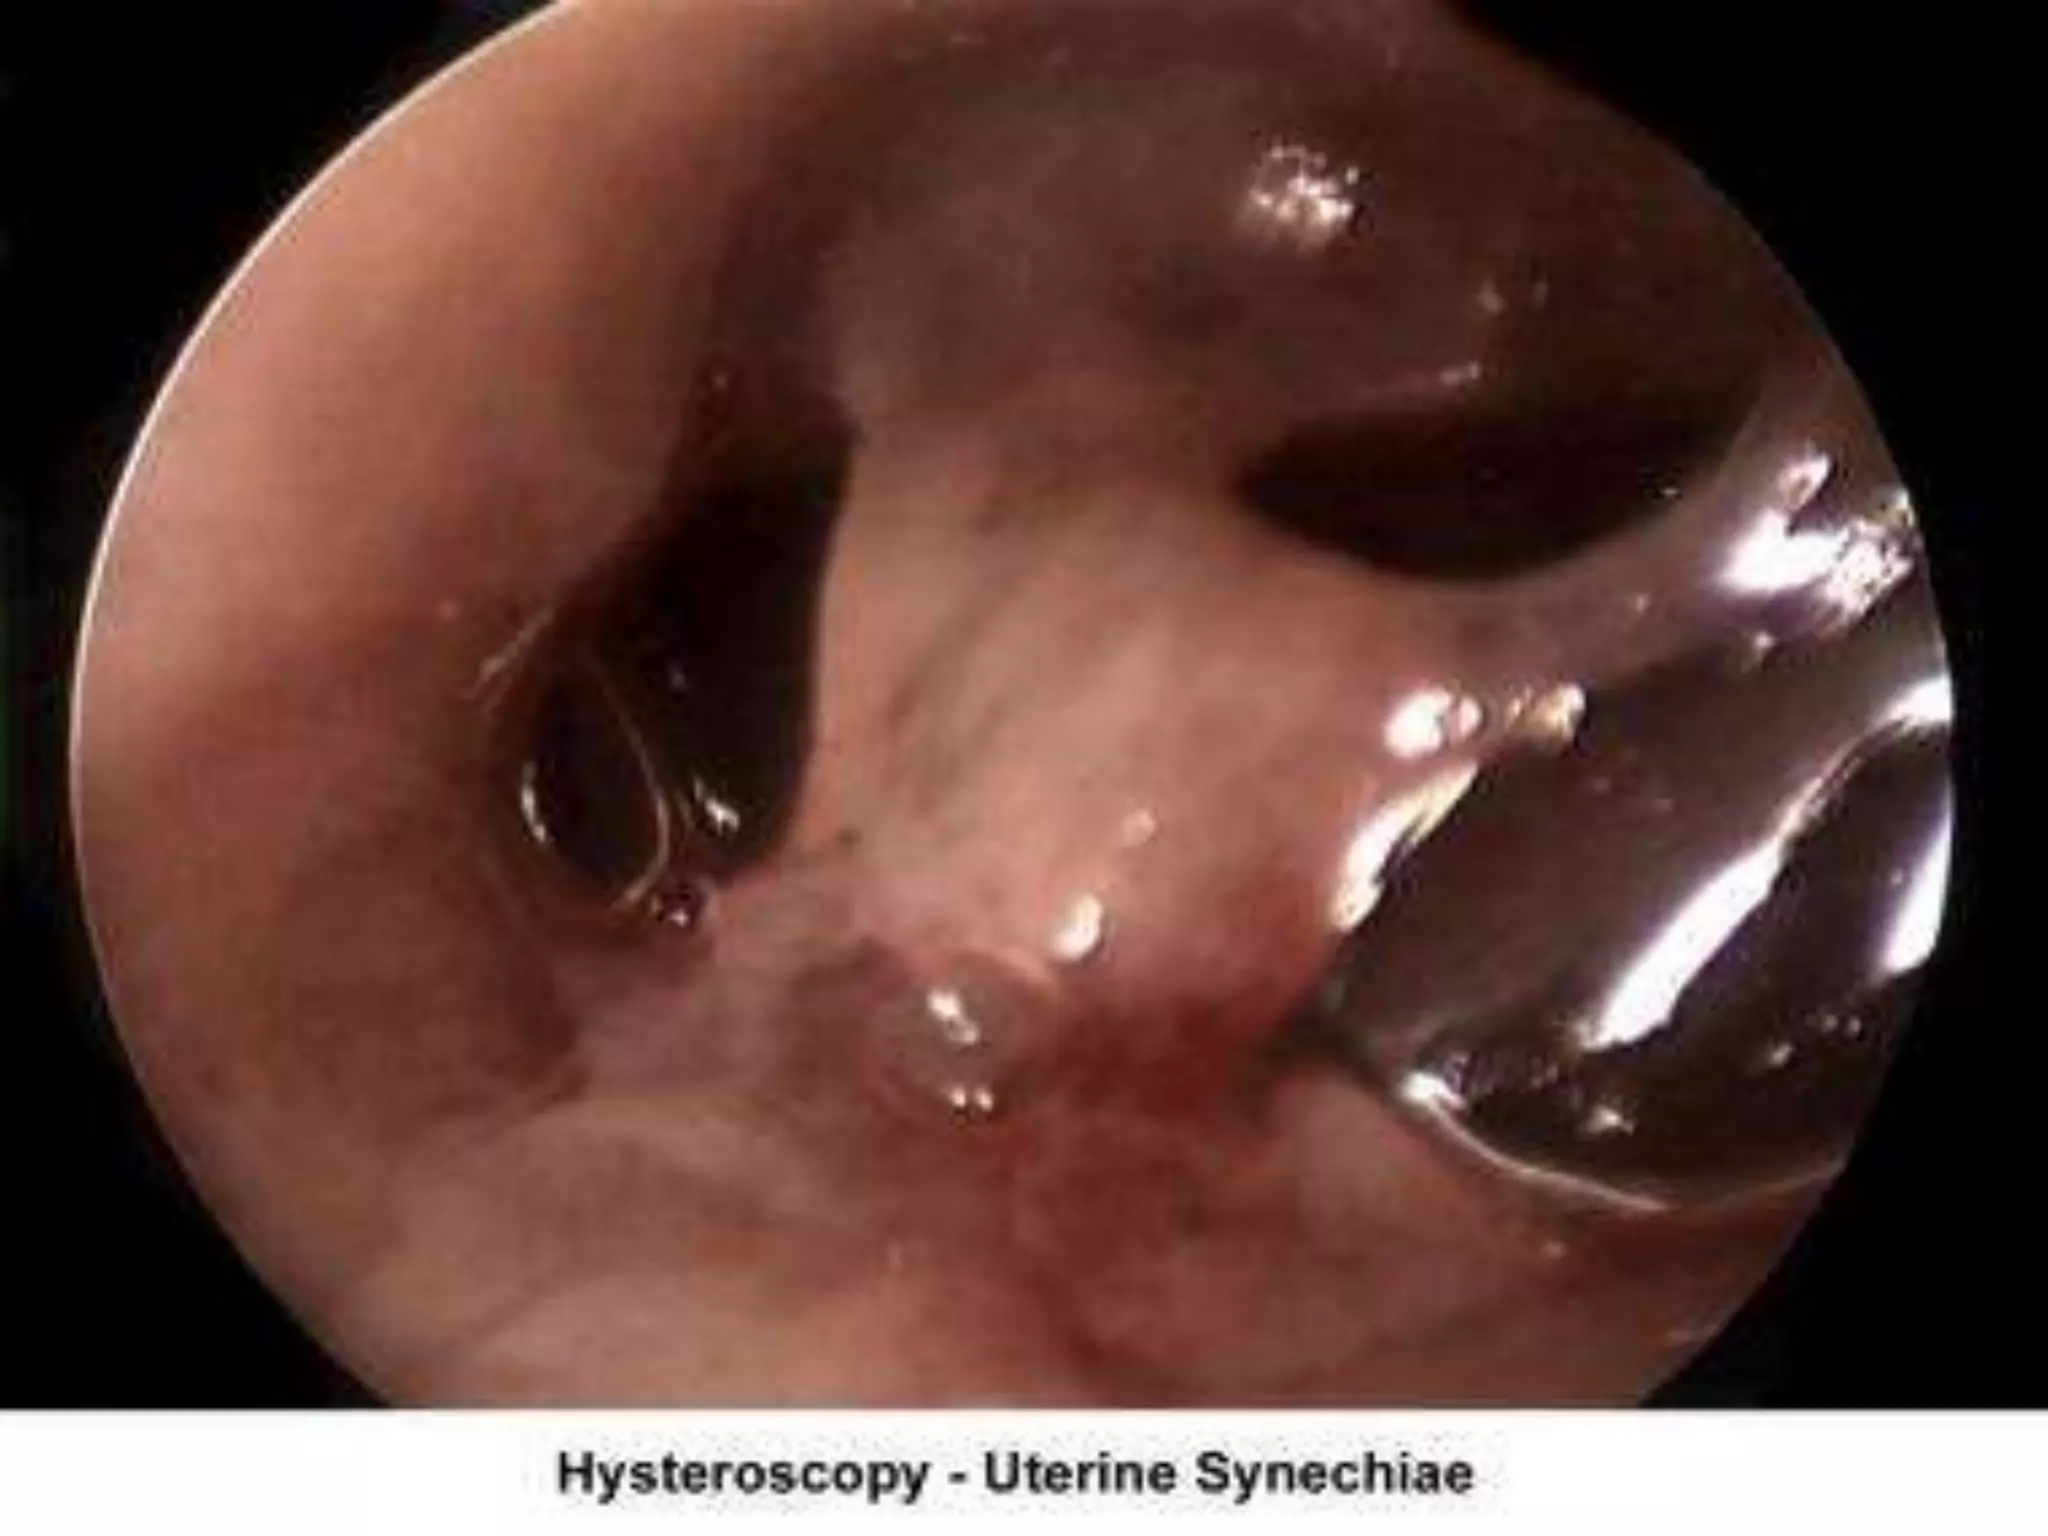

II. Acquired defects :

 Endometritis associated with a traumatic delivery,

dilatation and curettage, intrauterine device, or any

instrumentation (eg, myomectomy, hystrescopy) of

the endometrial cavity may create intrauterine

adhesions or synechiae (ie, Asherman syndrome),

with partial or total obliteration of the endometrial

cavity.

V.Hysteroscopy :

 is a method of direct visualization of the endometrial

 It allows both the diagnosis and treatment of

endometrial pathology.

 treatment of pathologies such as uterine synechiae,

endometrial polyps, submucous myomas, and the

removal of foreign bodies (eg, intrauterine devices).

In combination with specially designed catheters, it

can be used to perform tubal cannulation

Hysteroscope show endometrial pathologies .